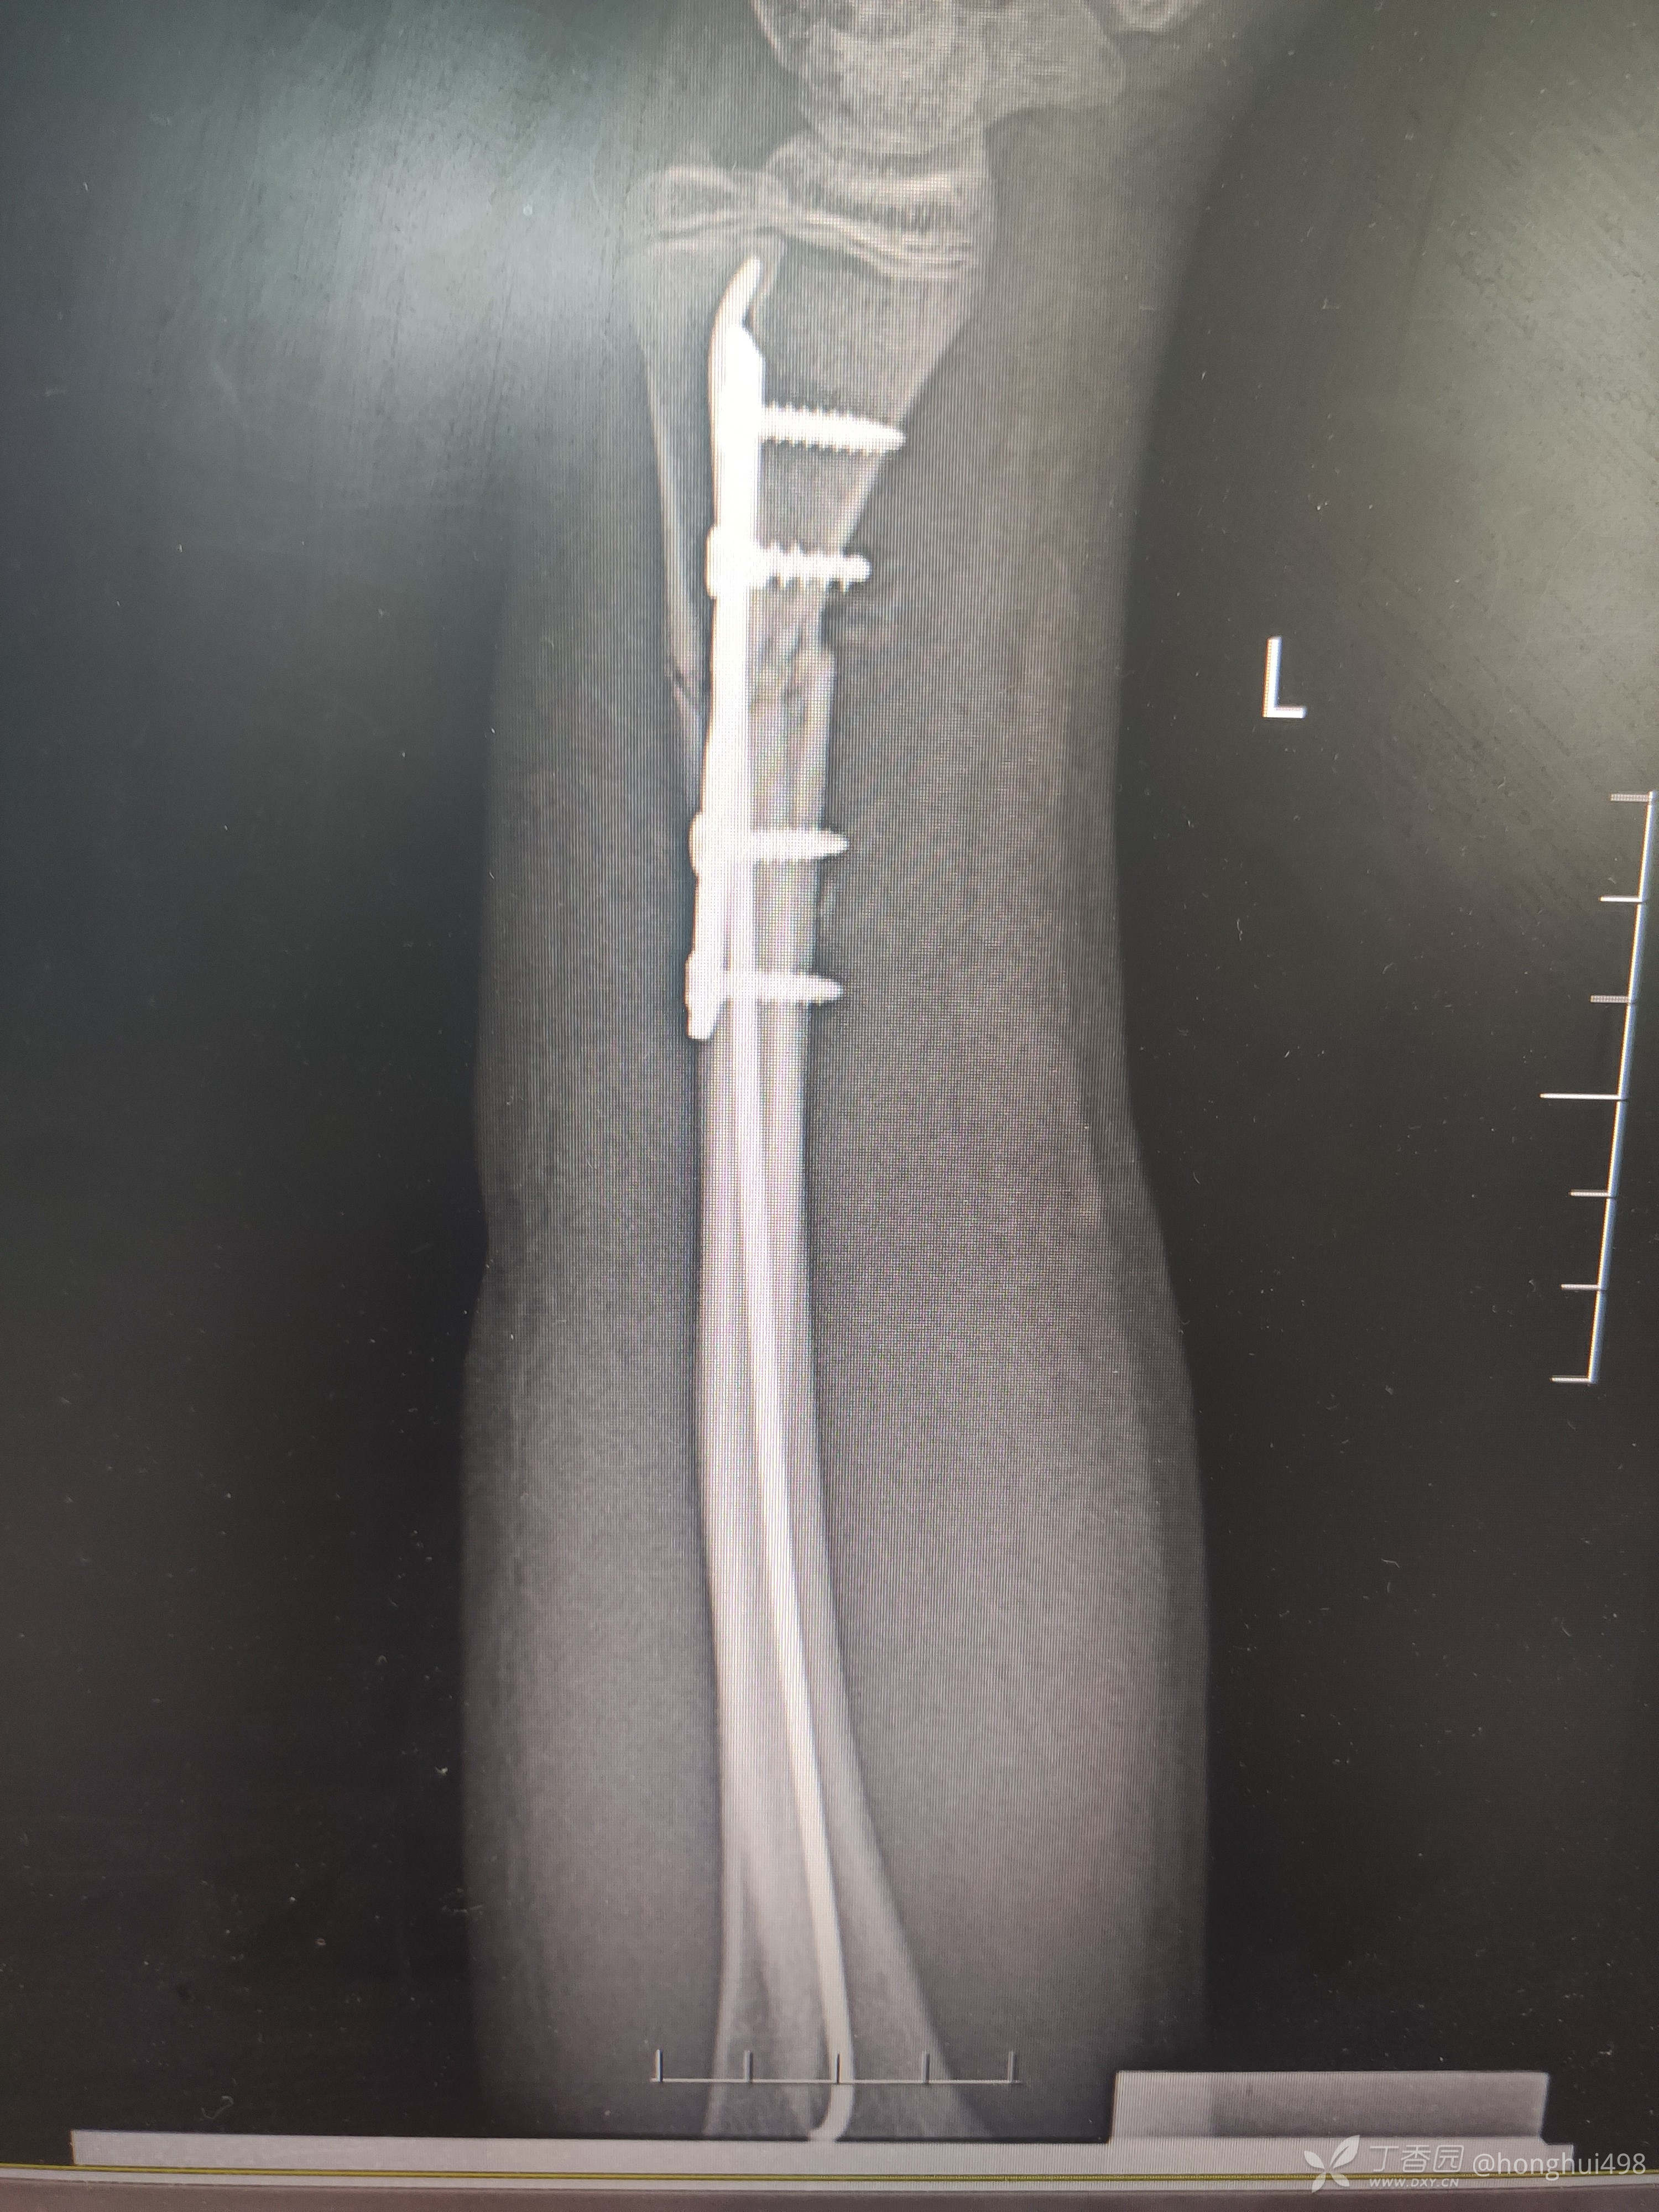

男性,14岁,摔倒致伤,左尺桡骨双骨折,肾病综合征。第一次受伤时手法整复,保守治疗两周后复查再次移位,二次入院手术治疗,术前计划桡骨闭合复位顺行髓内钉固定,术中发现复位不佳,切开复位钢板固定。